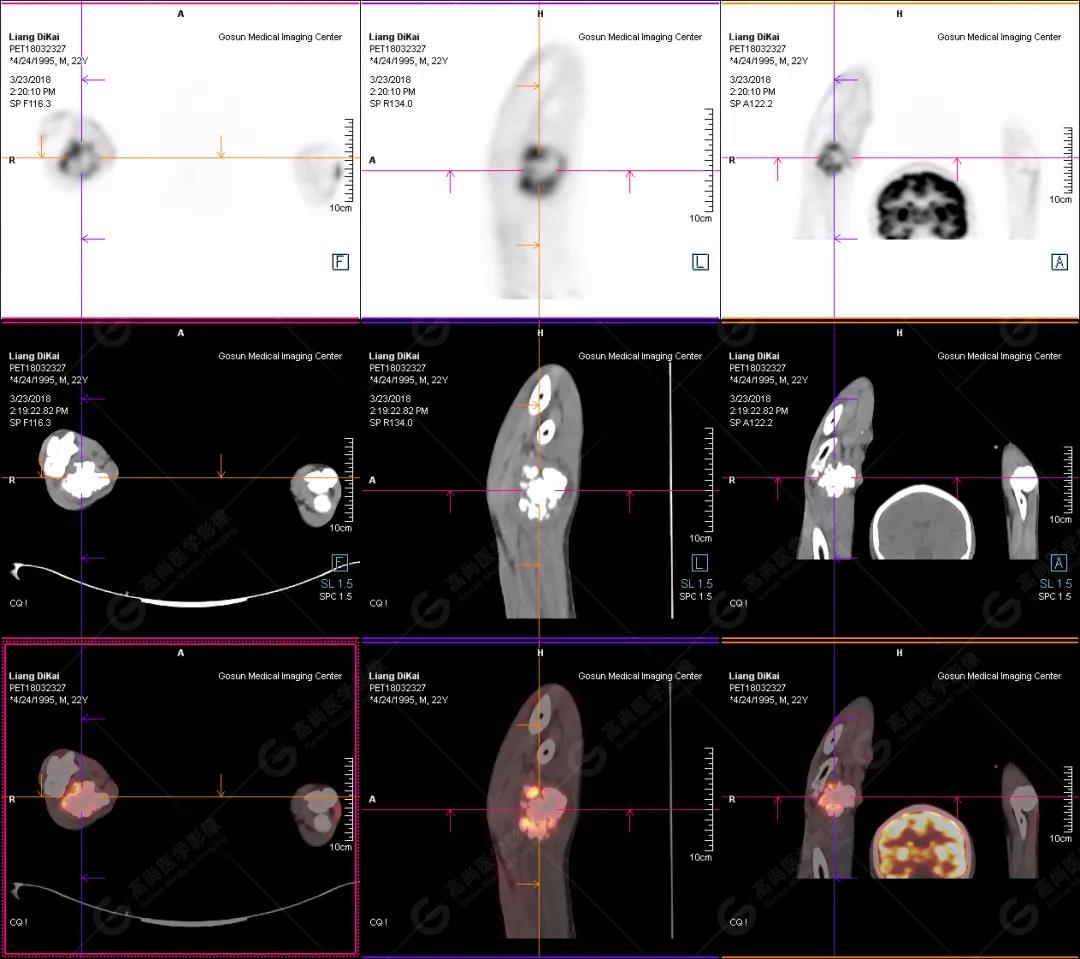

1.右肘關(guān)節(jié)周圍、骶尾部皮下、雙側(cè)臀部、盆腔左側(cè)壁及左側(cè)大腿根部肌肉、肌間隙多發(fā)結(jié)節(jié)狀、片塊狀及不規(guī)則巨塊狀高密度鈣化灶,伴代謝不均勻輕度增高,考慮為鈣質(zhì)沉著癥;

鈣質(zhì)沉著癥:是不溶性鈣鹽沉積于組織所產(chǎn)生的疾病。分為特發(fā)性、轉(zhuǎn)移性和營養(yǎng)不良性。特發(fā)性鈣質(zhì)沉著癥多原因不明,轉(zhuǎn)移性鈣質(zhì)沉著癥繼發(fā)于鈣磷代謝障礙性疾病,如甲狀旁腺功能亢進(jìn)、多發(fā)性骨髓瘤、腎功能不全使磷酸鹽潴留等,本例病例既為甲狀旁腺功能亢進(jìn)引發(fā)鈣質(zhì)沉著典型表現(xiàn)。